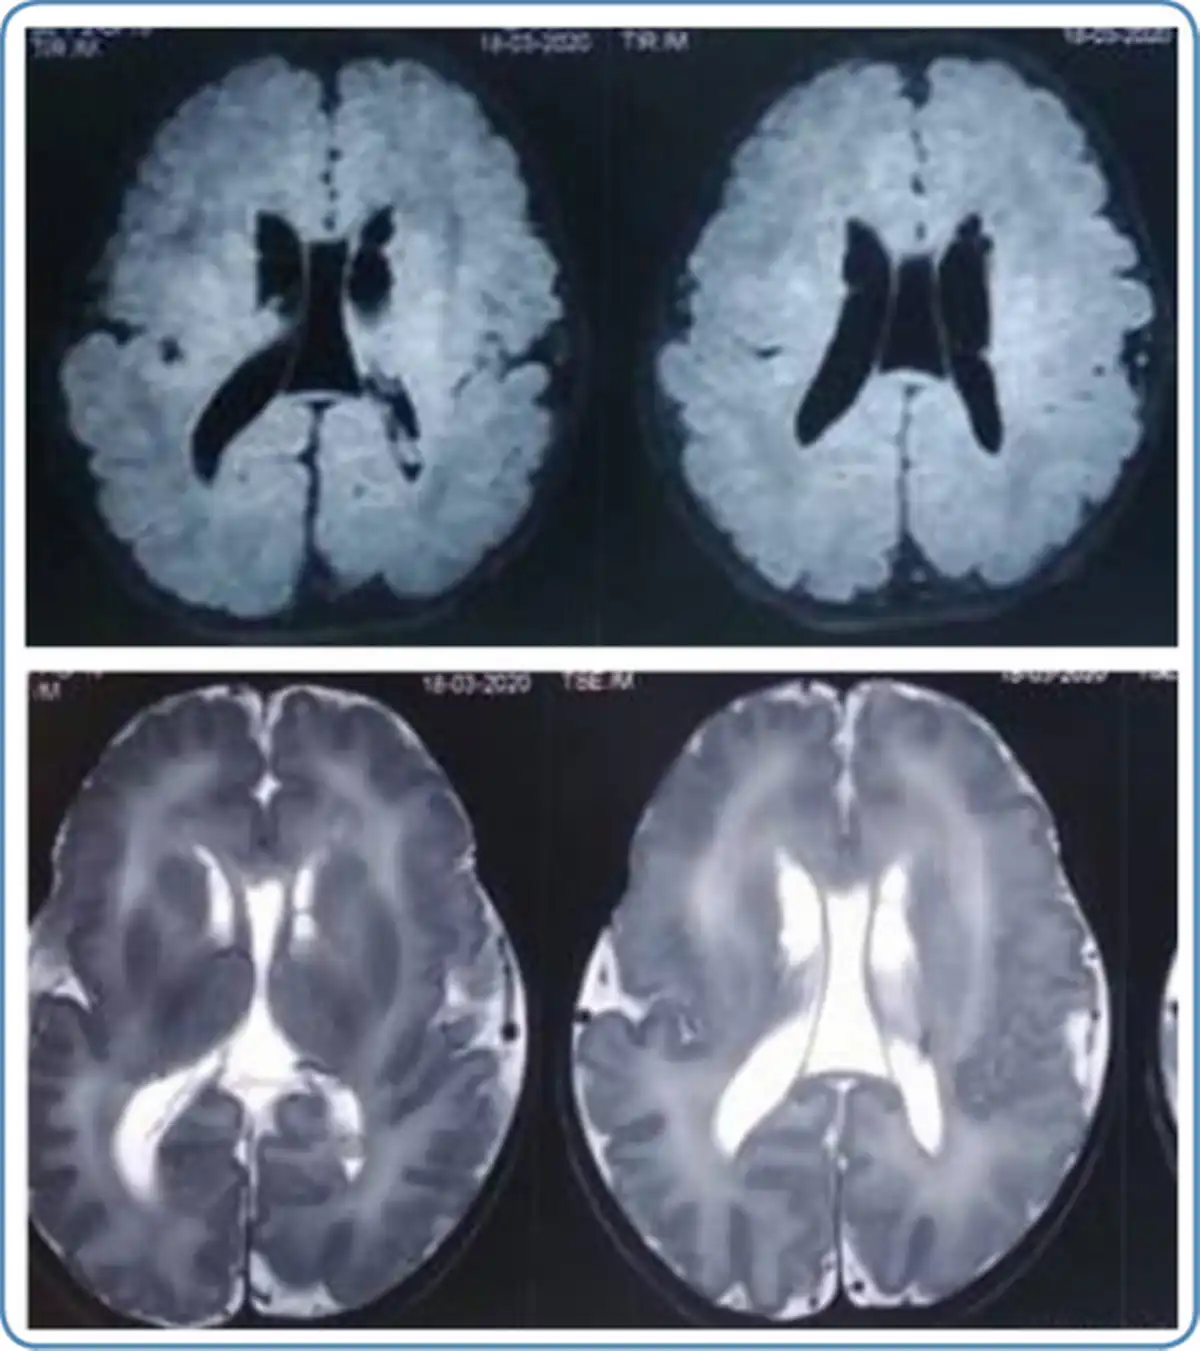

Neuroimaging findings

In peroxisomal disorders, specific findings in magnetic resonance imaging (MRI) of the brain are seen only in Zellweger syndrome (Figure 7) and X-ALD. In other peroxisomal disorders, MRI brain findings may provide clues to the diagnosis. MRI brain findings in peroxisomal disorders are listed in Table 4. Typical findings of the MRI brain may not be found in the initial stages of the disease in peroxisomal disorders as they evolve gradually during the disease course. In such a scenario biochemical workup and genetic evaluation would help in the diagnosis.

Figure 7

MRI brain findings in Zellweger syndrome 6A.T2 weighted MRI brain axial view showing germinolytic cysts 6B. T1 weighted MRI brain axial view showing diffuse polymicrogyria